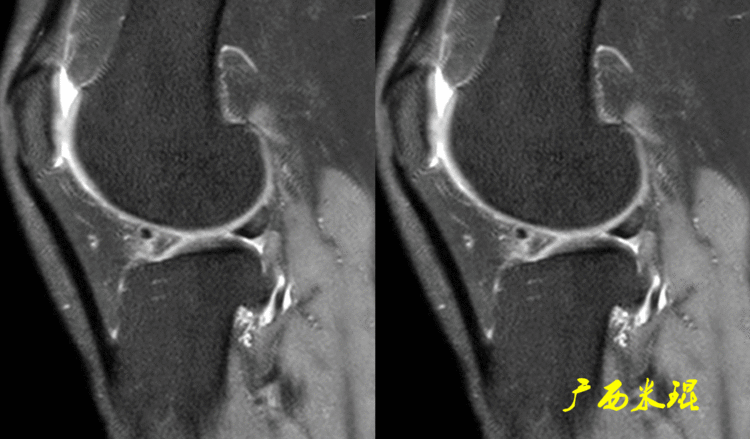

(3)半月板缝合后的裙边如果病人有半月板缝合的手术史,特别是较长的纵裂以及桶炳状撕裂的缝合,由于半月板对合不够整齐、或者缝合的松紧度不一致等等原因,术后也常常可以见到裙边。

下面矢状位MR是内侧半月板后角纵形撕裂缝合手术后,半月板外观完整,无分离,缝合处小片状稍高信号,这个高信号几乎不可能消失(半月板损伤痕迹永远存在)。

内侧半月板后角纵形撕裂缝合手术后,半月板外观完整,无分离,缝合处的线状稍高信号一般情况下也永久存在。

如同下面这张MR,左侧图像为手术前的,右侧图像为手术后的,术后病人疼痛等症状仍然存在,复查MR见外侧半月板前角分层,半月板前角的处理是有一定难度的,有经验的医生会考虑可能是手术者对前角的处理不够熟悉,没有通过另外的办法处理半月板前角的水平裂,不过也只能是猜测而已。所以,对于半月板术后的评估,症状的消失比MR重要!